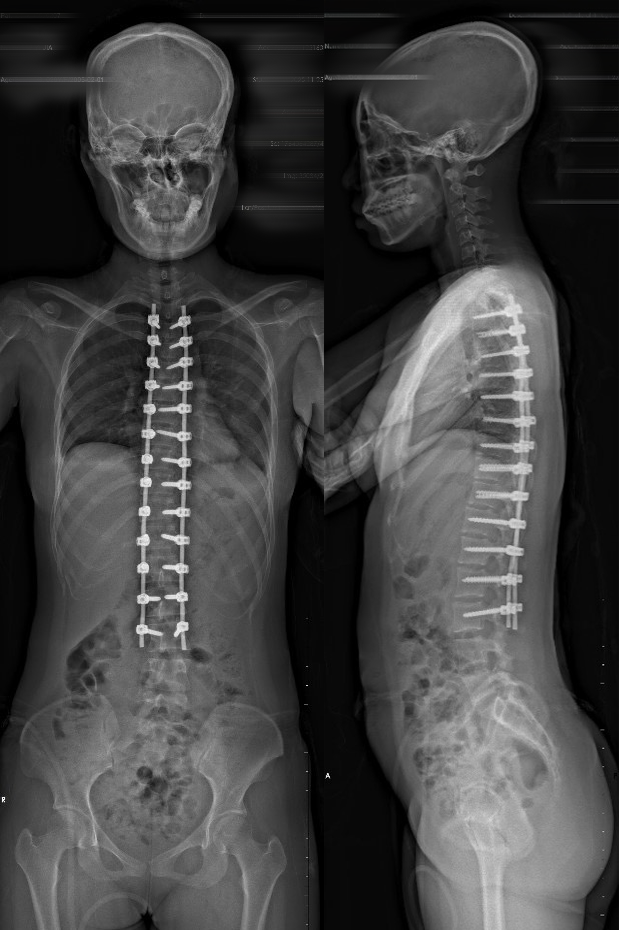

术后影像资料

术后检查影像

手术规划:固定节段T3-L3,I级截骨,矫形,去旋转。

手术操作:

沿T3-L3棘突,双侧骨膜下剥离至关节突或横突,经T3-L3置入椎弓根螺钉,透视下内固定位置好。

去除T5-T12棘突及部分下关节突。于双侧上连接棒,去旋转,凹侧撑开,凸侧加压,锁定。

T3-L3横突及椎板表面去皮质化,植骨。引流管引流,缝合切口。